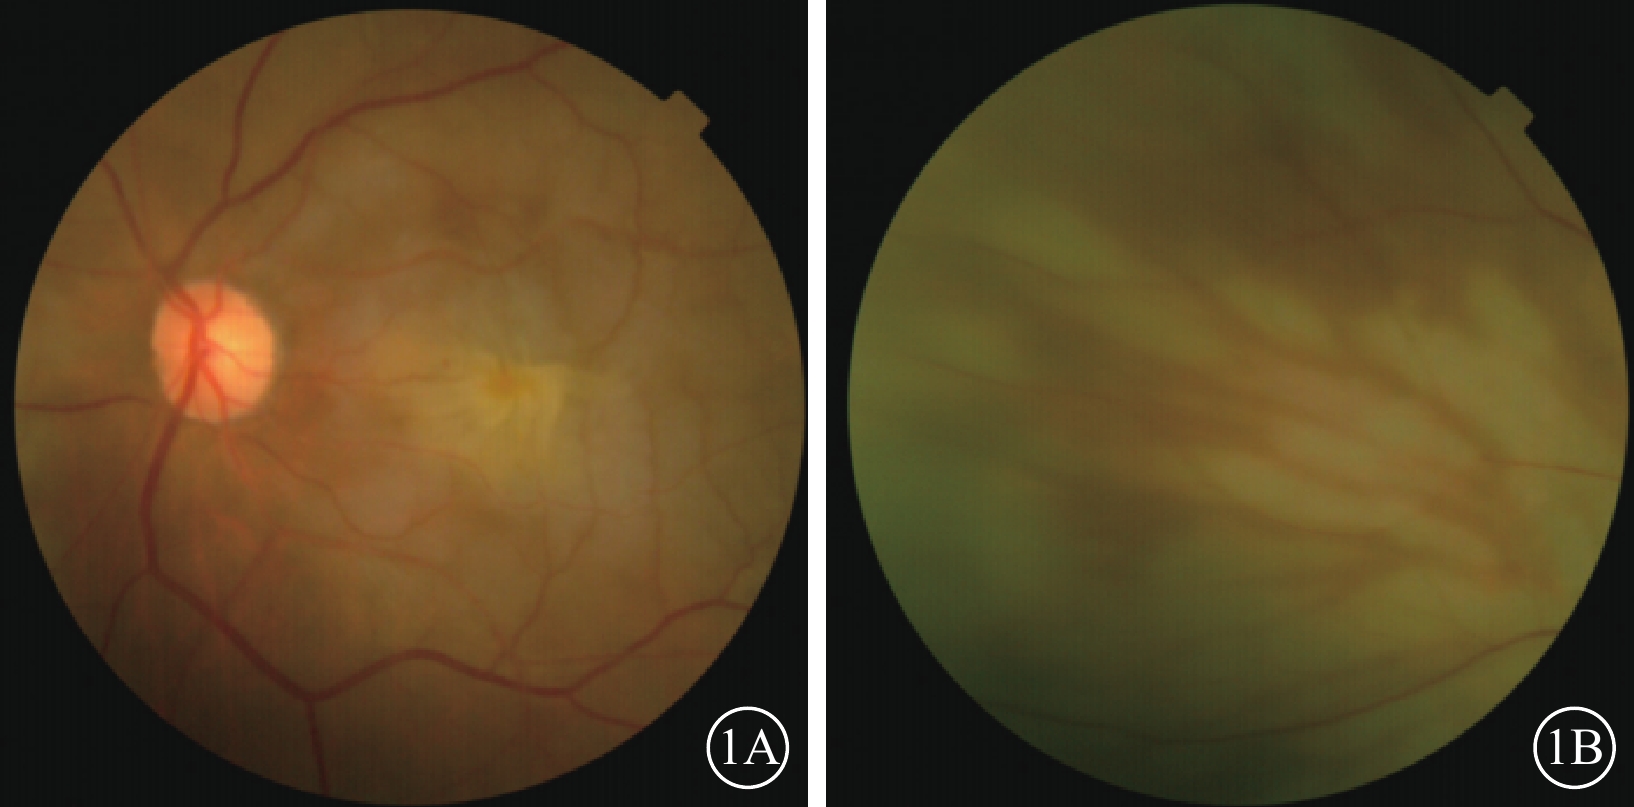

患者女,77歲。因左眼視力下降8個月加重1個月于2017年10月26日至北京大學第三醫院眼科中心就診。既往曾有晨起時一過性左眼黑矇史;否認高血壓、糖尿病等全身病史。甘油三酯輕度升高,出凝血時間正常。眼部檢查:左眼視力0.1,矯正不能提高;右眼視力0.2,矯正視力0.3。左眼眼壓(IOP)20 mmHg(1 mmHg=0.133 kPa)。晶狀體核性混濁;眼底可見黃斑前膜。右眼晶狀體混濁,其余眼前節及眼底檢查未見明顯異常。診斷:(1)左眼白內障;(2)左眼黃斑前膜。于10月28日在局部麻醉下行左眼白內障超聲乳化IOL植入、23G玻璃體切割手術(PPV)。手術參數:超聲乳化瓶高85 cm,PPV時IOP 28 mmHg。手術時間45 min,過程順利。手術后第1天,左眼視力眼前數指。角膜輕度水腫;眼底視盤邊界清楚,色澤正常,黃斑區輕度水腫。IOP 37 mmHg,給予降眼壓藥物控制。手術后第2天,患者自述晨起時左眼黑矇,檢查左眼視力上方眼前手動。眼底視盤邊界清楚,顏色淡;后極部視網膜灰白水腫,無櫻桃紅斑(圖1A),視網膜動脈內血流中斷;視盤鼻側見羽毛狀灰白水腫楔狀區域(圖1B),與視網膜血管分布不一致。IOP 18 mmHg。FFA檢查,視盤和脈絡膜充盈遲緩,視網膜中央動脈14″ 73開始充盈,可見動脈前鋒,21″17靜脈尚未完全充盈;25″92視盤鼻側開始顯現由邊界清楚羽毛狀強熒光拼成的楔形區域,隨時間延長熒光增強,但始終邊界清楚(圖2A)。次日ICGA檢查,脈絡膜充盈遲緩,至10′42″20時視盤鼻側開始出現脈絡膜強熒光區,與FFA所見形態部位一致(圖2B)。OCT檢查,視網膜內層彌漫強反射,層次不清,黃斑中心凹處呈皺褶狀隆起(圖3),鼻側病灶區脈絡膜層面異常反射不顯著。頸動脈彩色多普勒血流顯像(CDFI)檢查,雙側頸動脈硬化斑塊形成。心臟CDFI檢查,左室泵功能正常,舒張功能減低;主動脈瓣輕度關閉不全。神經內科初步診斷:頸內動脈系統短暫性腦缺血發作。頭頸部CT血管造影(CTA)檢查,雙側頸內動脈起始部血管壁混雜斑塊形成,管腔變窄。頭顱CT檢查,多發腔隙性腦梗死,軟化灶。腦白質疏松,腦萎縮。未行頭頸部數字減影血管造影。24 h橈動脈動態血壓監測結果:白天平均血壓121/60 mmHg,脈壓差60.7 mmHg;夜間平均血壓110/51 mmHg,脈壓差59.7 mmHg。最終臨床診斷:(1)左眼脈絡膜三角綜合征;(2)左眼視網膜中央動脈阻塞(CRAO);(3)左眼內低灌注。

左眼手術后第2天彩色眼底像。1A示后極部,視網膜灰白水腫,呈淡黃色皺褶狀水腫隆起;1B示視盤鼻側,可見羽毛狀灰白水腫楔狀區域

左眼手術后第2天彩色眼底像。1A示后極部,視網膜灰白水腫,呈淡黃色皺褶狀水腫隆起;1B示視盤鼻側,可見羽毛狀灰白水腫楔狀區域

圖1

左眼手術后第2天彩色眼底像。1A示后極部,視網膜灰白水腫,呈淡黃色皺褶狀水腫隆起;1B示視盤鼻側,可見羽毛狀灰白水腫楔狀區域

圖1

左眼手術后第2天彩色眼底像。1A示后極部,視網膜灰白水腫,呈淡黃色皺褶狀水腫隆起;1B示視盤鼻側,可見羽毛狀灰白水腫楔狀區域